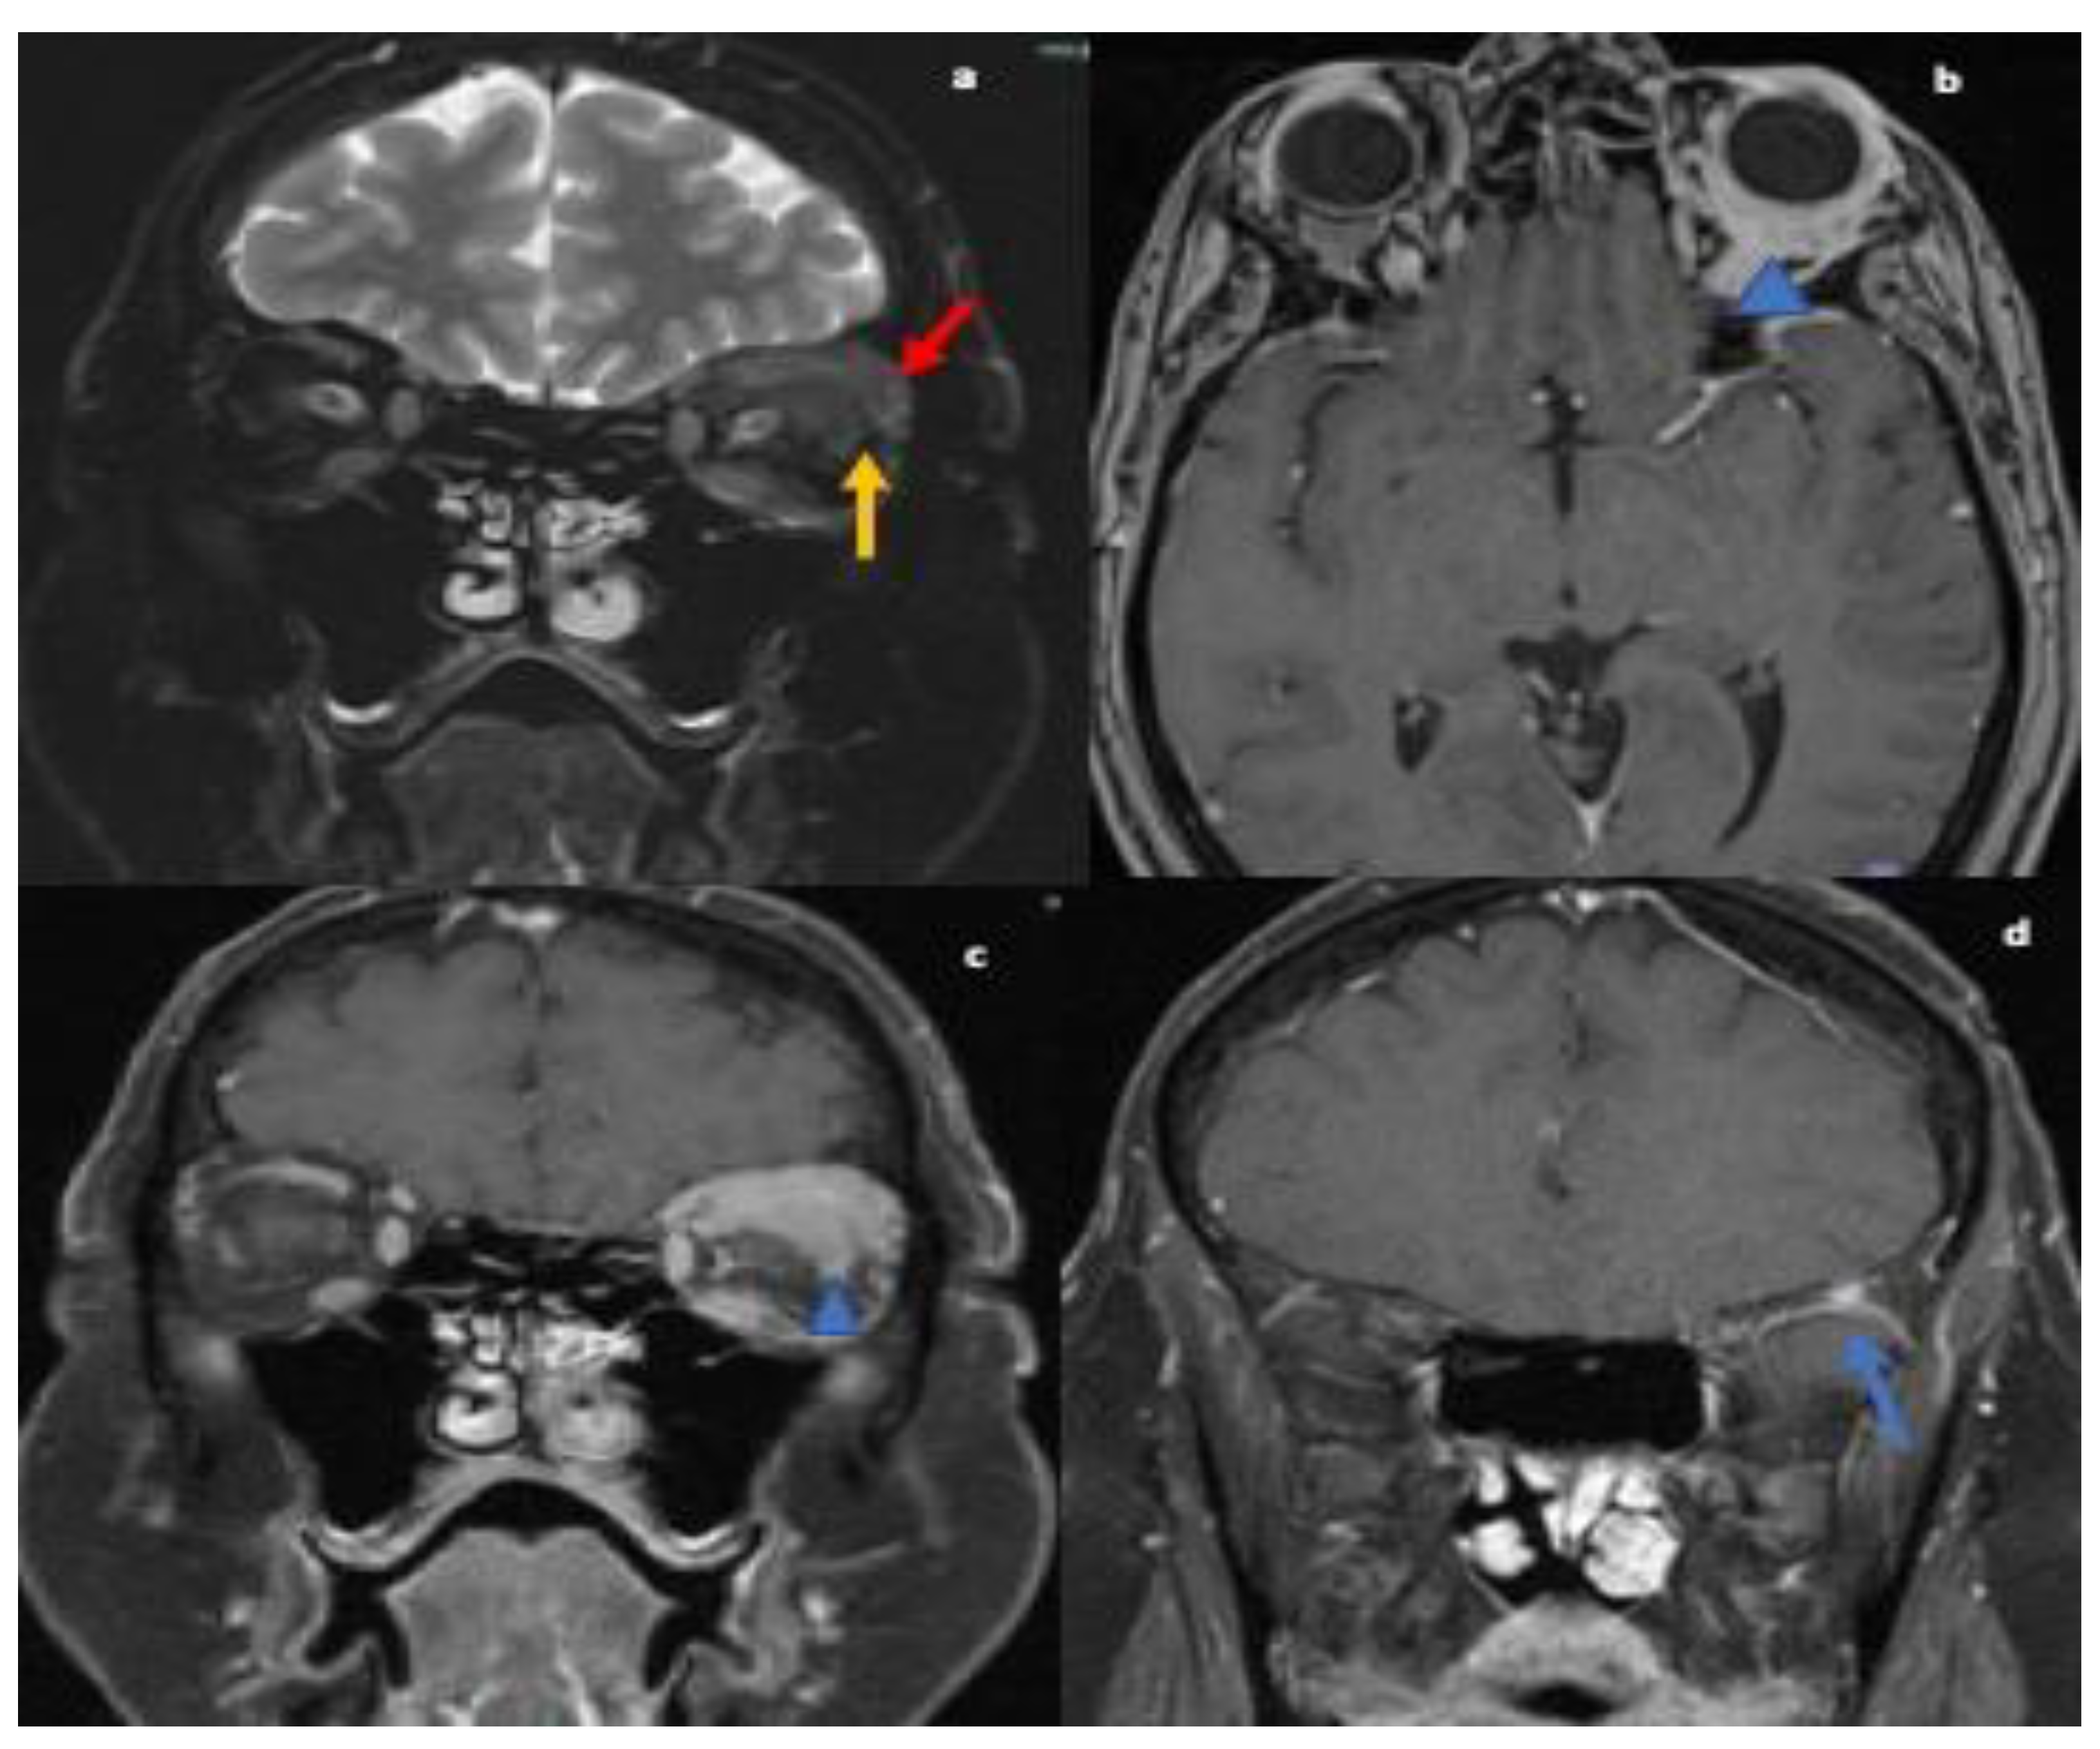

The serum autoimmune and infectious work up were unremarkable. MRI orbits showed soft tissue thickening and enhancement in the left orbit with enlarged extraocular muscles, enlarged lacrimal gland and osseous involvement of the sphenoid bone (refer Figure 2). Differential at that time included cellulitis and lymphoproliferative disorder. She was started on oral antibiotics followed by left orbitotomy and excision of the mass. Biopsy of the mass revealed granulomas and the patient was diagnosed with orbital sarcoidosis. CT chest/abdomen/pelvis were without evidence of malignancy or systemic sarcoid. No lumbar puncture was performed as diagnosis was confirmed on biopsy.

Figure 2.

MRI orbit T2 fat-suppressed coronal images reveals nodular thickening of the left lacrimal gland (red arrow; (a)), superior and lateral recti muscles (yellow arrow; (a)). T1-weighted post contrast axial (b) and coronal images (c) showing corresponding enhancement within muscles, lacrimal gland and in intraconal orbits surrounding the globe (blue arrowhead).T1 weighted post contrast coronal image (d) reveals enhancing nodule in the greater wing of left sphenoid concerning for osseous involvement (blue arrow).

NS can affect the neurological system in various ways. One of these is cranial nerve involvement. Any of the cranial nerves can be involved in NS [11] but the most frequently reported is cranial nerve VII [1]. The first case in our series presented with lower motor neuron VII nerve palsy and VIII nerve involvement leading to a misdiagnosis of Bell’s palsy and ear infection. Multiple cranial nerve involvement, lesion within the brainstem and intramedullary lesions within the upper cervical spinal cord were seen on MRI were present in this case of NS. Despite treatment with steroids, the patient did not initially show improvement, complicating the case even further. The second case, initially diagnosed as orbital cellulitis, also demonstrated multiple cranial nerve involvement with ophthalmoplegia secondary to infiltration of the extraocular muscles due to granulomatous masses. The patient experienced loss of vision in the left eye due to surrounding inflammatory changes and mass effect. A subsequent biopsy confirmed the diagnosis of orbital sarcoidosis. Hence, cranial nerve involvement with other CNS lesions should raise suspicion for NS and treatment with steroids may not show a significant response initially.

The second case, initially diagnosed as orbital cellulitis, had second cranial nerve involvement with marked loss of vision in the left eye. There was also infiltration of extraocular muscles with pain upon eye movements and ophthalmoplegia due to granulomatous mass. Orbital sarcoid manifestations include thickening and enhancement of the intra-orbital and intracranial optic nerve and chiasm, optic atrophy and orbital masses. These are often mistaken as pseudotumor, glioma, meningioma of the optic nerve sheath, MS, or infectious etiology such as syphilis, lymphogranuloma venereum, leprosy, tularemia, torulosis, histoplasmosis, blastomycosis, and coccidioidomycosis [25,26,27,28,29]. Fast spin-echo fat suppressed axial and coronal T2, and T1 axial and coronal fat-suppressed contrast-enhanced MRI images are considered to be the standard protocol to investigate for intra-orbital or optic nerve disorders [30].